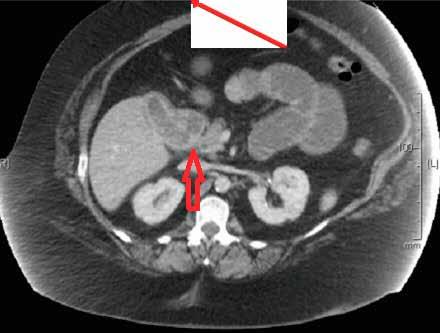

一名49岁的女性患者因上腹部疼痛伴恶性呕吐于当地医院急诊科就诊,两个月前患者因胆石症,胆总管扩张,梗阻性黄疸行内镜逆行行胰胆管造影术,,取出3块胆石,如图1、2。行腹部CT检查,提示小肠梗阻,胆石性肠梗阻,十二指肠瘘,如图3、4。患者立即行急诊手术治疗,术中发现扩张小肠有明显胆石阻塞及压迫痕迹,取出胆石,由于小肠压力过大,出现部分坏死,因此行小肠部分切除术,如图5。在距离回盲部60cm小肠处取出大小约3.5cm*3.5cm胆结石,如图3。用腹腔镜从Treitz韧带检查小肠,并未发现有残余结石,病人在手术后已康复,顺利出院。

图4 腹部CT提示胆囊十二指肠瘘